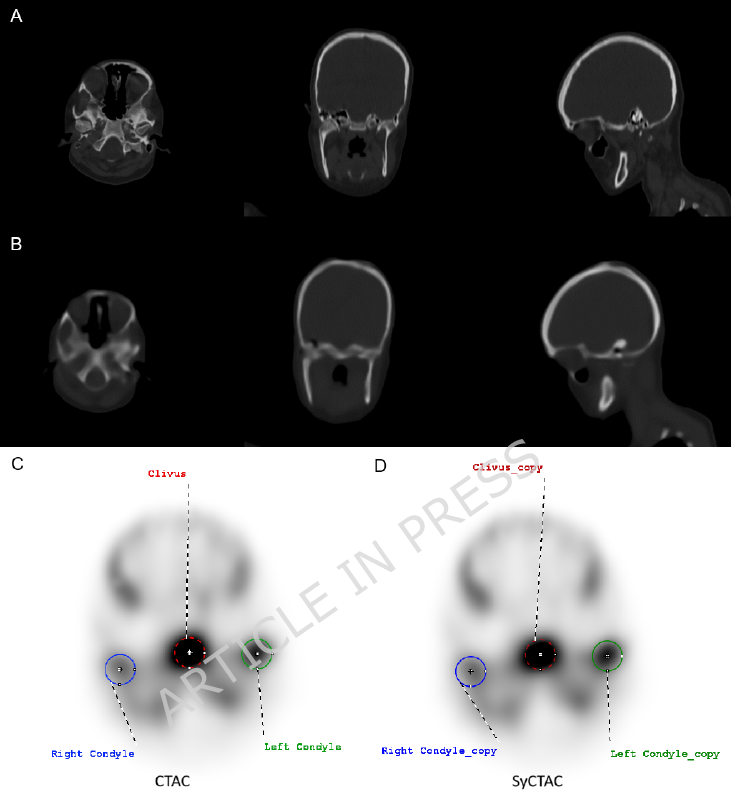

Axial, coronal and sagittal slices of CT (A) and SyCT (B) images.

Axial slices of the CTAC (C) and SyCTAC (D) images with spherical VOIs (diameter: 2 cm) placed over both condyles and the clivus.

During the evaluation, the right and left mandibular condylar regions were identified on the CT-s, spherical VOIs with a diameter of 2 cm were placed over both condyles on the CTAC images. Using the same approach, a 2 cm spherical VOI was also placed over the clivus region. Subsequently, the condylar and clivus VOIs were copied to the SyCTAC images in the identical positions. Based on the VOIs placed over the mandibular condyles and the clivus, SUVmax and SUVmean values were determined on both the CTAC and SyCTAC images and two kinds of uptake values (relative uptake fractions and relative uptake normalized to the clivus as reference area) were calculated.

Visual evaluations were independently performed by three nuclear medicine specialists, who reported no substantial differences between the SPECT images reconstructed with CT and those reconstructed with SyCT. Specifically, no differences were noted regarding image intensity display, lesion detectability, or the feasibility of VOI placement.